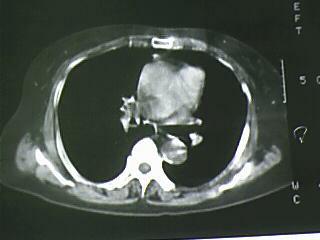

以下是引用bmw011在2009-4-14 19:14:00的发言:[br]右肺继发型肺结核---纵隔淋巴结多发钙化----左肺支扩。支持

以下是引用杀毒软件在2009-4-14 17:52:00的发言:[br]考虑---右肺继发型肺结核---纵隔淋巴结多发钙化----左肺支扩

以下是引用黑白光影在2009-4-14 20:36:00的发言:[br]右肺继发型肺结核;左下慢性支气管炎性病变。